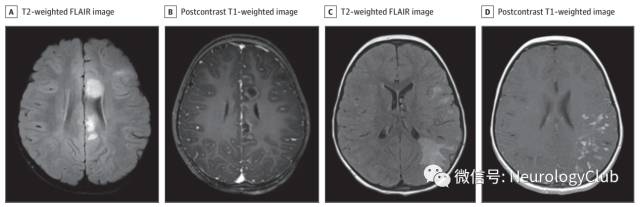

年轻女性,既往体健,表现为思睡,视物成双和左侧六、七颅神经麻痹1周。头颅MRI可见脑干、左侧额叶、左侧扣带回和左侧顶叶T2/FLAIR异常信号伴片状强化,不伴有弥散受限(图A-B)。颈椎MRI未见明显异常。脑脊液化验无殊,未见肿瘤细胞,寡克隆带阴性。血清AQP4抗体阴性。初步考虑急性播散性脑脊髓炎(ADEM),予大剂量激素冲击5天,后改口服泼尼松治疗1月,3周内患者恢复至基线水平。

15月后患者症状再次出现,表现为构音障碍和进行性共济失调不伴有意识状态改变2周。行头颅MRI可见先前幕上病灶已好转,但新出现脑干和左侧颞顶叶T2/FLAIR较大病灶伴片状强化(图C-D)。头颅MRA无殊。脑脊液检查提示轻度淋巴细胞增多(白细胞计数11/μL,其中中性粒细胞6,淋巴细胞6,单核细胞2),红细胞计数1/μL,糖57mg/dL,总蛋白水平39g/dL。

(图:A-B:首次发病时的头颅MRI;可见左侧额叶FLAIR高信号病灶伴强化;C-D:第二次发作时的头颅MRI;可见左侧颞顶叶FLAIR高信号伴片状强化)